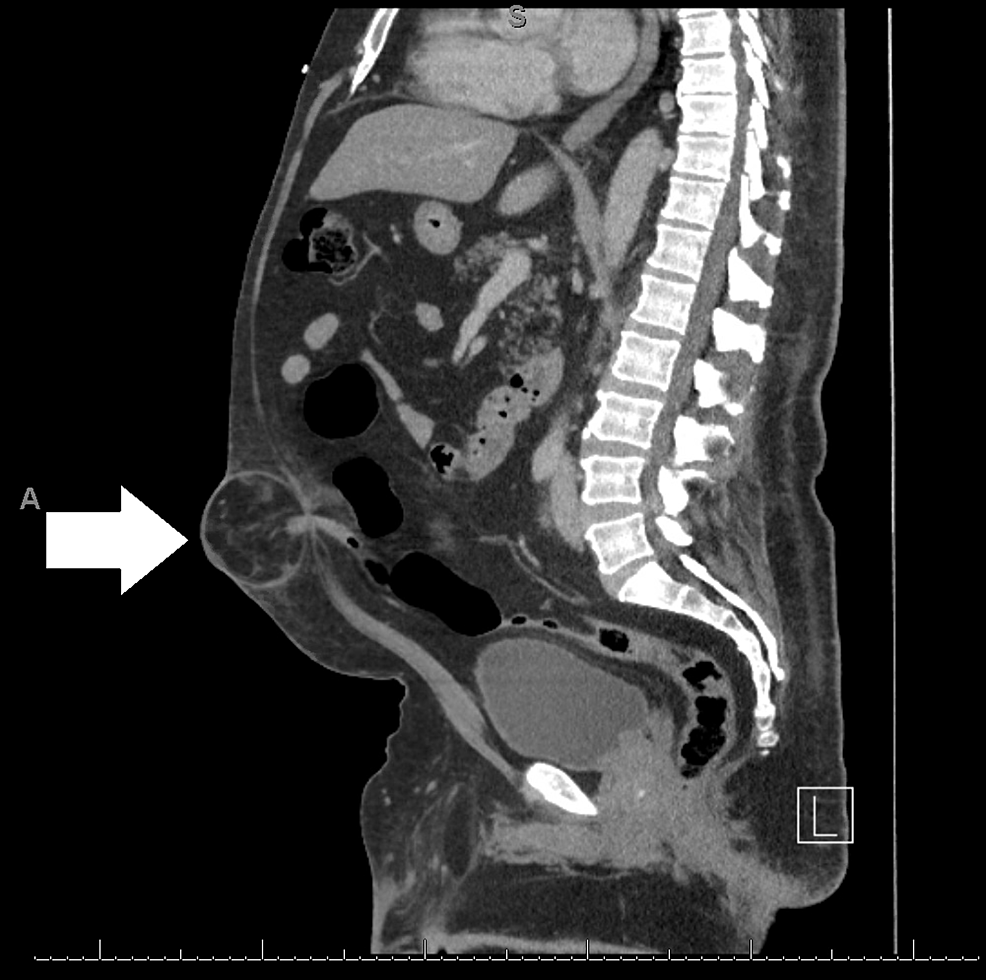

- CT and MRI images